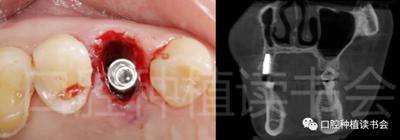

5.3.5 考慮到初始植入扭矩未達(dá)到30N.cm,采用外覆”倍菱“膠原蛋白+縫線固定的方式關(guān)閉創(chuàng)口的方案(圖18)。

圖18 創(chuàng)口使用”倍菱“膠原蛋白保護(hù),促進(jìn)愈合。

5.3.6 術(shù)后即刻CBCT(美亞光電)檢查種植體軸向及深度良好(圖19)。

圖19 術(shù)后即刻CBCT確認(rèn)種植體頰、

舌側(cè)骨板完整,并保持了足夠的厚度。